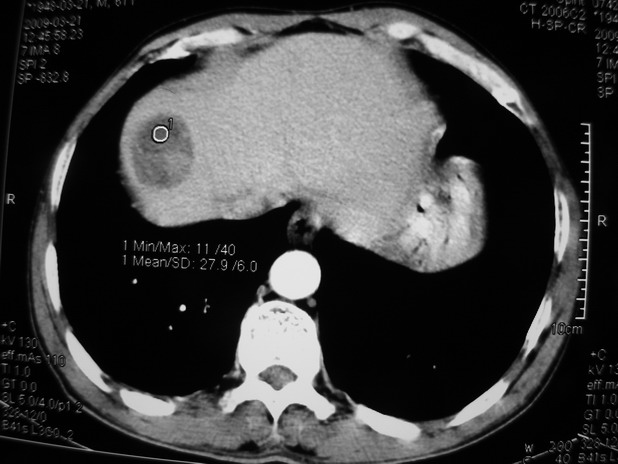

以下是引用余辉在2009-3-21 21:36:00的发言:[br]图像太乱了,建议楼主直接将强化数据按顺序列出来,病灶位置较表浅薄,有肝炎病史,灶内实性成分有显著强化,动脉期约60hu,考虑肝癌可能性大,进一步检查。